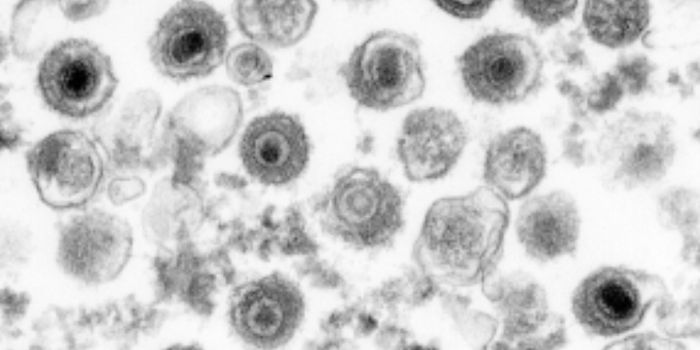

NOV 10, 2019MicrobiologyFor the first time since 2000, researchers have identified a new subtype of HIV.

FEB 02, 2016MicrobiologyUniversity of Minnesota researchers found a new, more affordable way to treat HIV. The RNA-based drug 5-azacytidin ...

DEC 15, 2018Cell & Molecular BiologyResearchers have been trying to create a vaccine for HIV, the virus that causes AIDS, for decades.